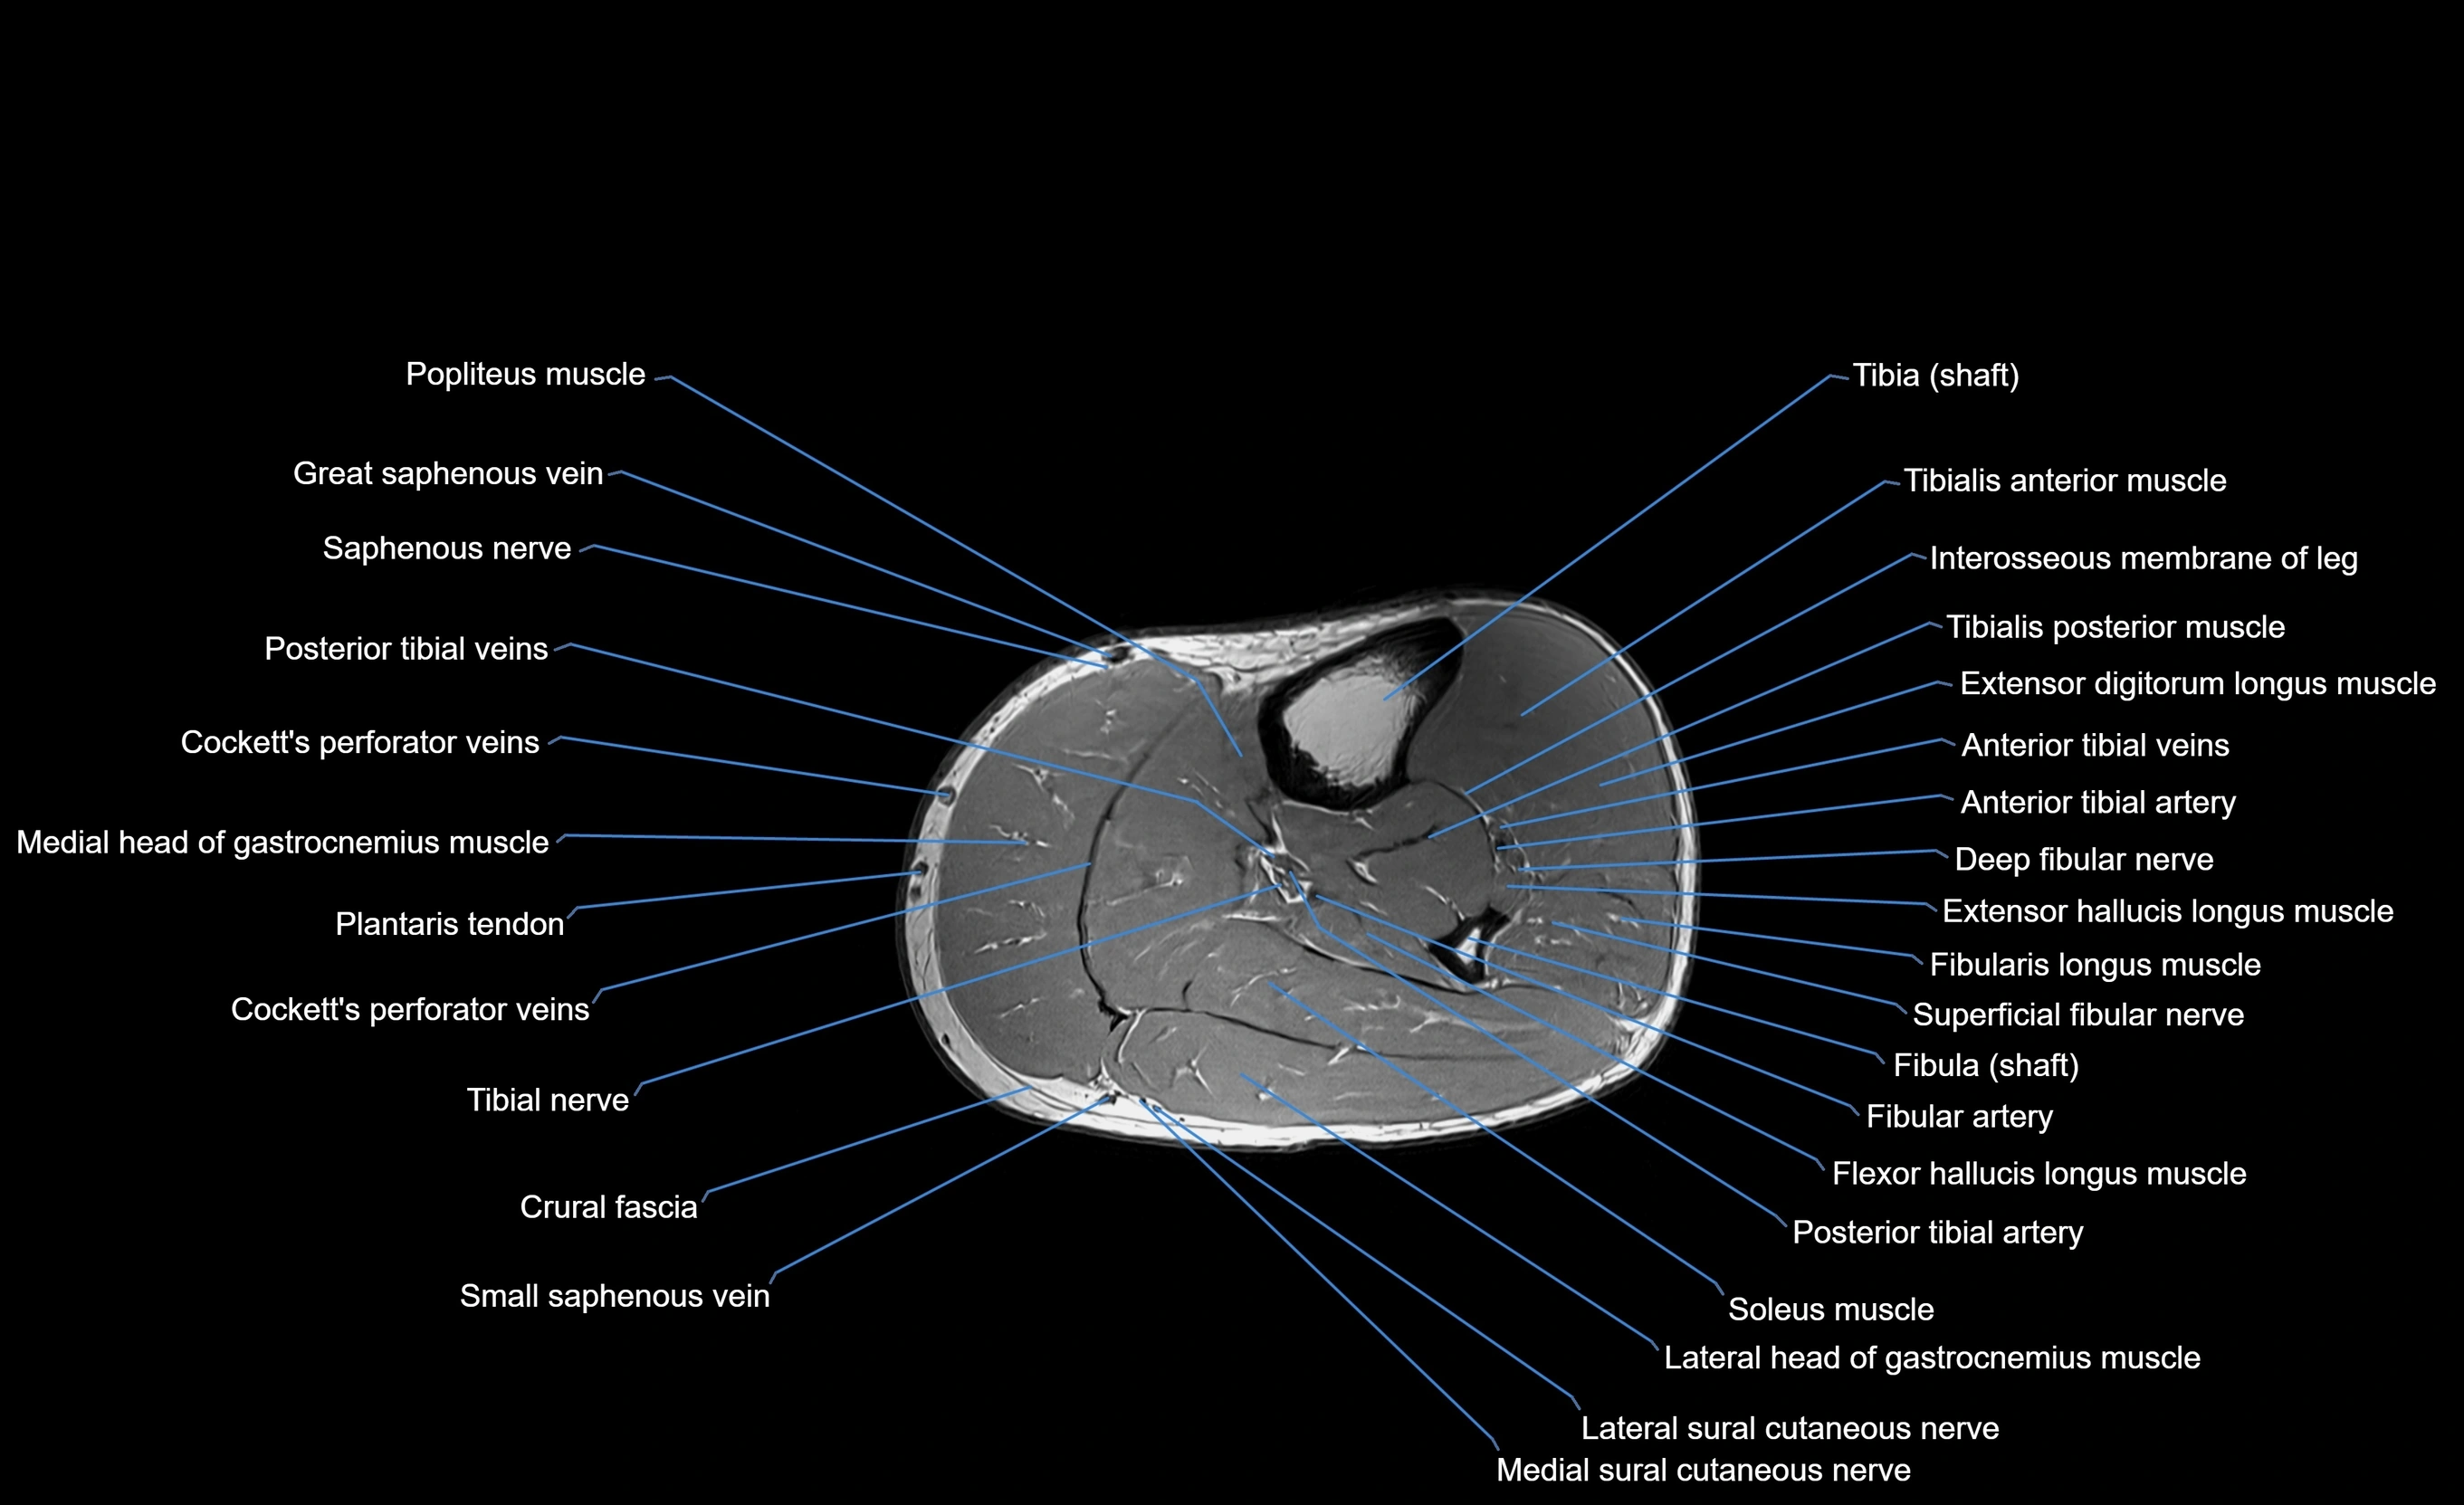

MRI image